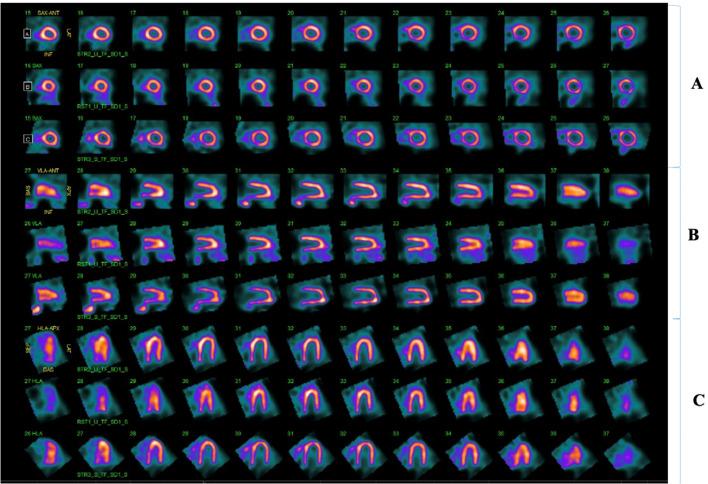

This case report describes a 40-year-old male who presented to the emergency department (ED) with chest pain. Initial diagnostic workup was concerning for a congenital cardiac anomaly, further imaging revealed complete congenital absence of the pericardium (CAP) which is a rare condition. Multimodality cardiac imaging including cardiac computed tomography angiogram (CCTA) was used to confirm the diagnosis of CAP. We briefly discuss various clinical presentations of CAP along with potential complications and other anomalies that could be associated with pericardial agenesis.

本病例报告描述了一名40岁男性,他因胸痛被送往急诊科。初步诊断检查怀疑有先天性心脏异常,进一步的影像学检查显示为完全性先天性心包缺如(CAP),这是一种罕见的病症。包括心脏计算机断层扫描血管造影(CCTA)在内的多模态心脏成像用于确诊CAP。我们简要讨论了CAP的各种临床表现以及可能与心包发育不全相关的潜在并发症和其他异常情况。